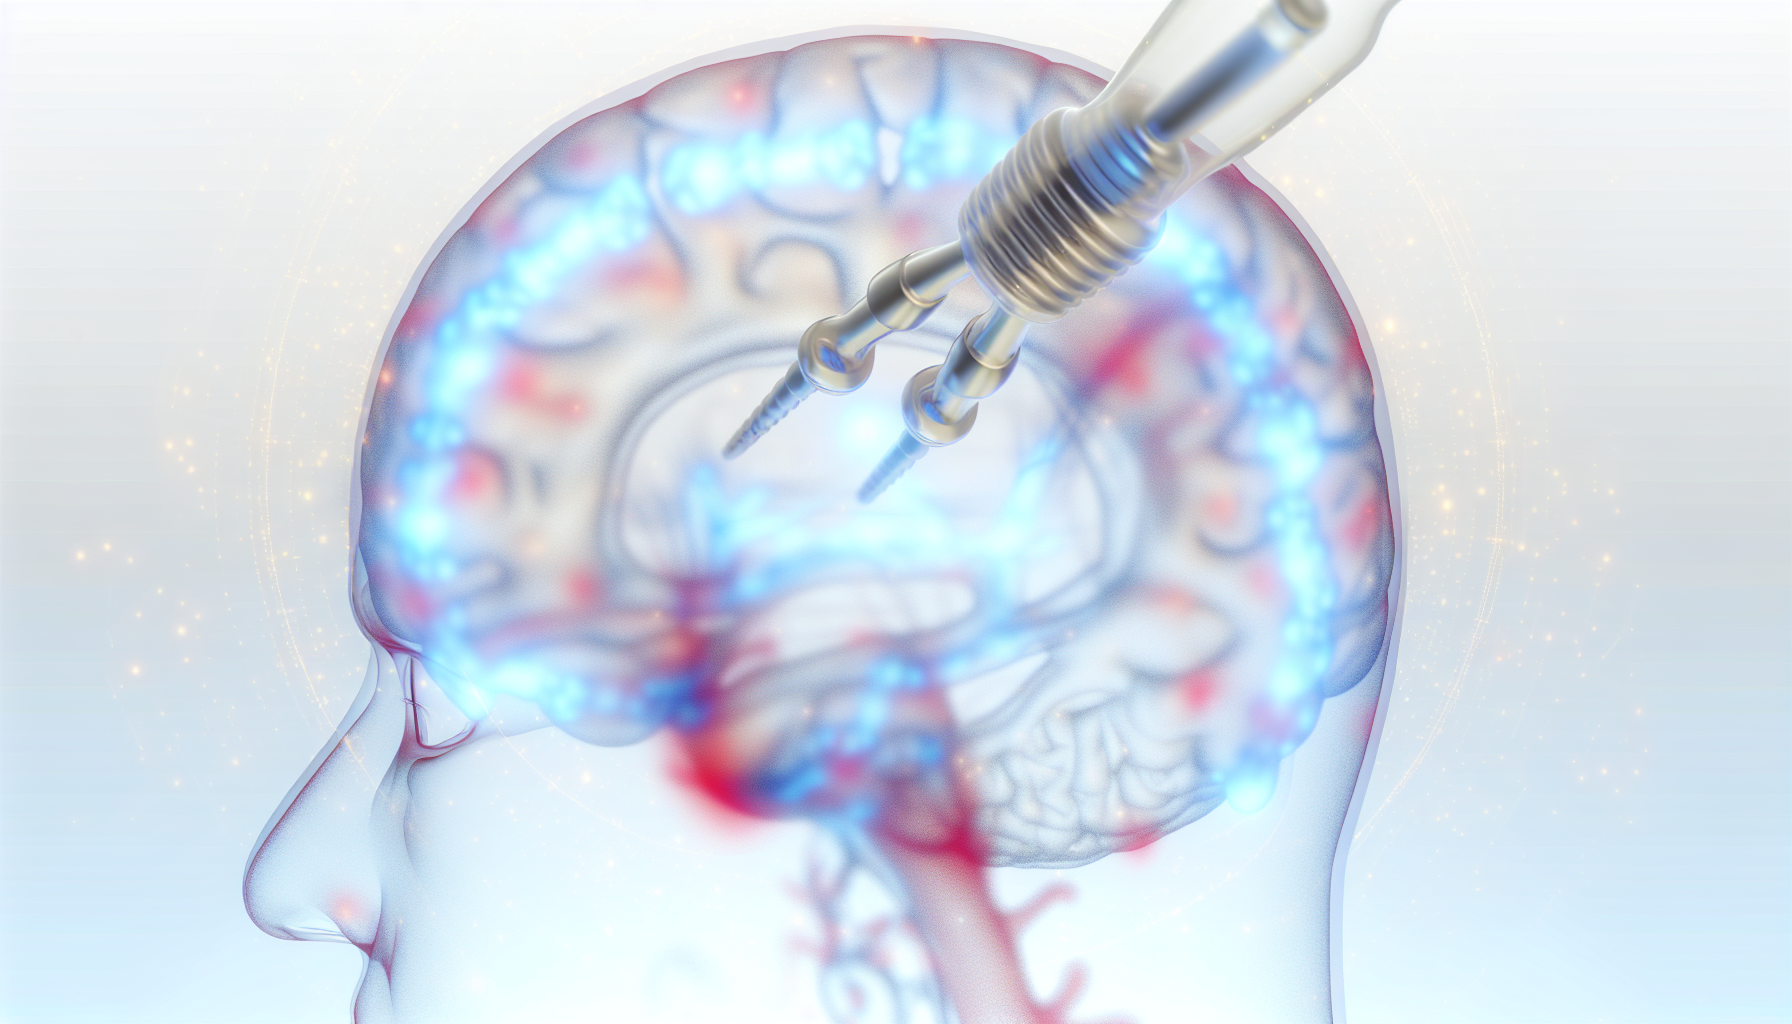

Read more1 Innovative Neural Implant Technique Promotes Skull Regrowth for Safe Brain Access 2

Introduction to the Breakthrough Neural Implant Technique A groundbreaking study...